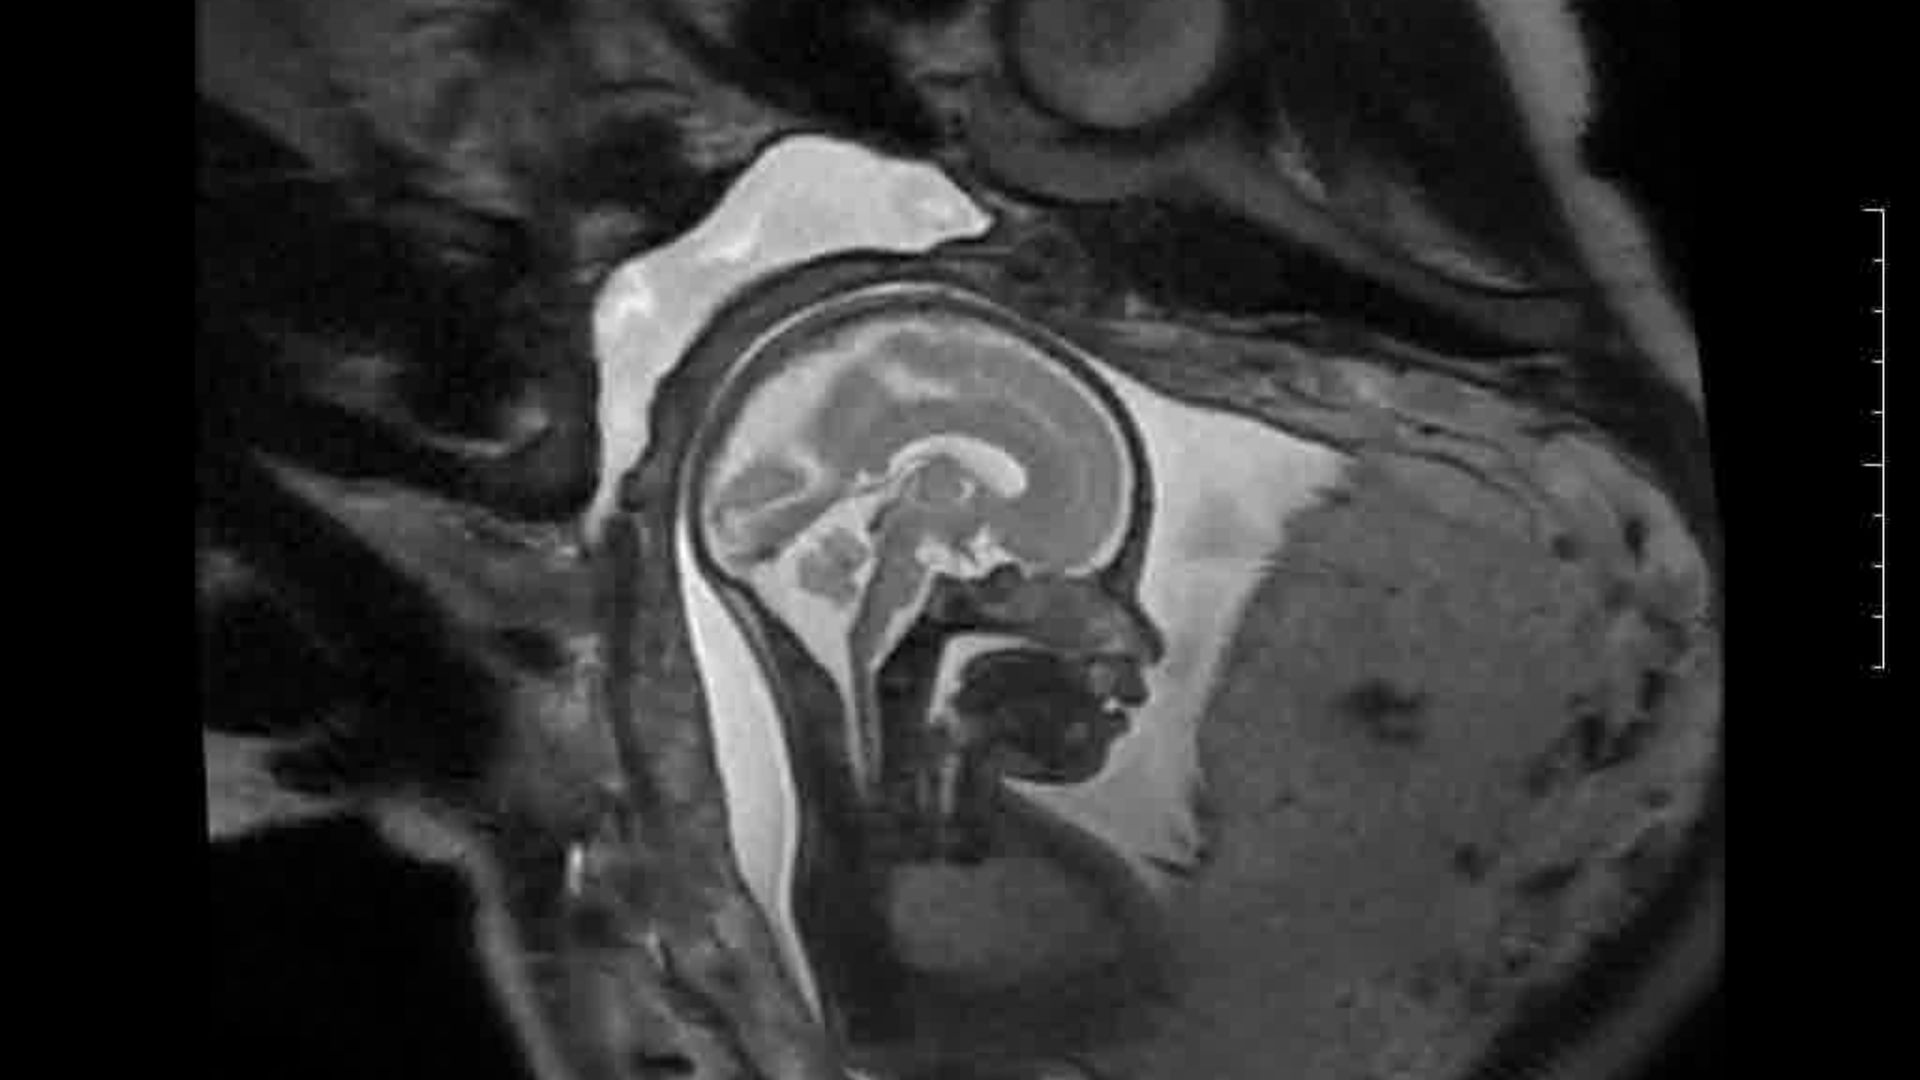

L’Université Paris Cité franchit une nouvelle étape dans le domaine de l’imagerie médicale anténatale avec l’acquisition d’un système d’Imagerie par Résonance Magnétique (IRM) 1,5T ARTIST™ de GE HealthCare. Cet équipement de pointe renforce les capacités de la Plateforme LUMIERE à l’hôpital Necker-Enfants malades, plateforme intégrée de soins, de recherche clinique et d’enseignement en imagerie médicale de la femme enceinte, du fœtus et du placenta.

Une plateforme au service de la recherche et des patientes enceintes

L’inclusion de ces patientes, depuis leur accueil jusqu’à la réalisation des examens d’imagerie, puis l’analyse des images et l’interprétation des résultats par des équipes expertes, enrichit une base de données structurée, unique au monde, au service de la recherche et de l’innovation en imagerie anténatale et en médecine fœtale.